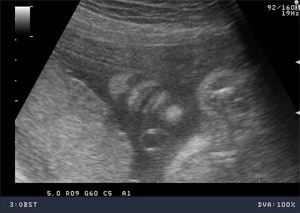

USG 3D / 4D

W nowoczesnych wysokiej klasy aparatach ultrasonograficznych istnieje możliwość przetwarzania danych z badania dwuwymiarowego co umożliwia pokazywanie obrazów trójwymiarowych badanych struktur płodu w czasie rzeczywistym.

Ultrasonografia trójwymiarowa 3D pozwala na uzyskanie statycznych obrazów przestrzennych, które otrzymywane są w procesie obróbki komputerowej danych z badania dwuwymiarowego. Ultrasonografia 4D pozwala na uwidocznienie dynamicznego przestrzennego obrazu.

Ta nowa prezentacja (prezentacja 4D) pochodzi od dodania czwartego wymiaru jakim jest czas. Badanie płodu metodą 4D pozwala nie tylko na obrazowanie przestrzenne płodu ale również pozwala na obserwację ruchów twarzy, obserwację otwierania i zamykania oczu, ruchów języka, ssania palców. Przy korzystnym ułożeniu płodu, w odpowiednim wieku ciążowym ( najlepiej pomiędzy 15. a 35. tygodniem ciąży) możliwa jest diagnostyka szeregu wad rozwojowych płodu. Badanie 4D pozwala też na precyzyjne obrazowanie rozwoju płodu i umożliwia podejrzenie wyglądu dziecka, którego wygląd jest niemal identyczny z jego rzeczywistym wyglądem.

Zastosowanie techniki 3D i 4D ma szczególne zastosowanie w położnictwie. Umożliwiają precyzyjną ocenę narządów wewnętrznych płodu, np. serca, mózgowia, kręgosłupa, twarzy oraz w sposób istotny pozwalają na zwiększenie wykrywalności wad budowy płodu .